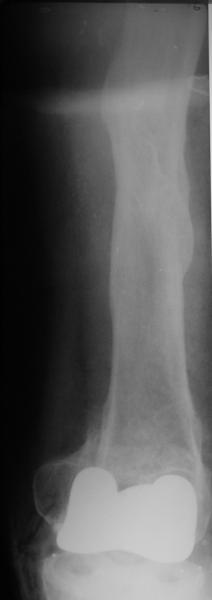

Отправитель: Alexander Chelnokov 02 Июнь 2004, 13:58

TAC> idea to osteotomize the femur shaft to compensate for the prior shaft malunion

TAC> was clever and should work fine.

The "idea" was an emergency appeared when the nail tip proceeded to the fracture level and became targeting anteriorly to the distal fragment.

TAC> I can't actually see the osteotomy on either radiograph. Is it more proximal

TAC> than we see in these radiographs or so well aligned as to be not visible?

The osteotomy was perfromed trough the fracture site. See the image.